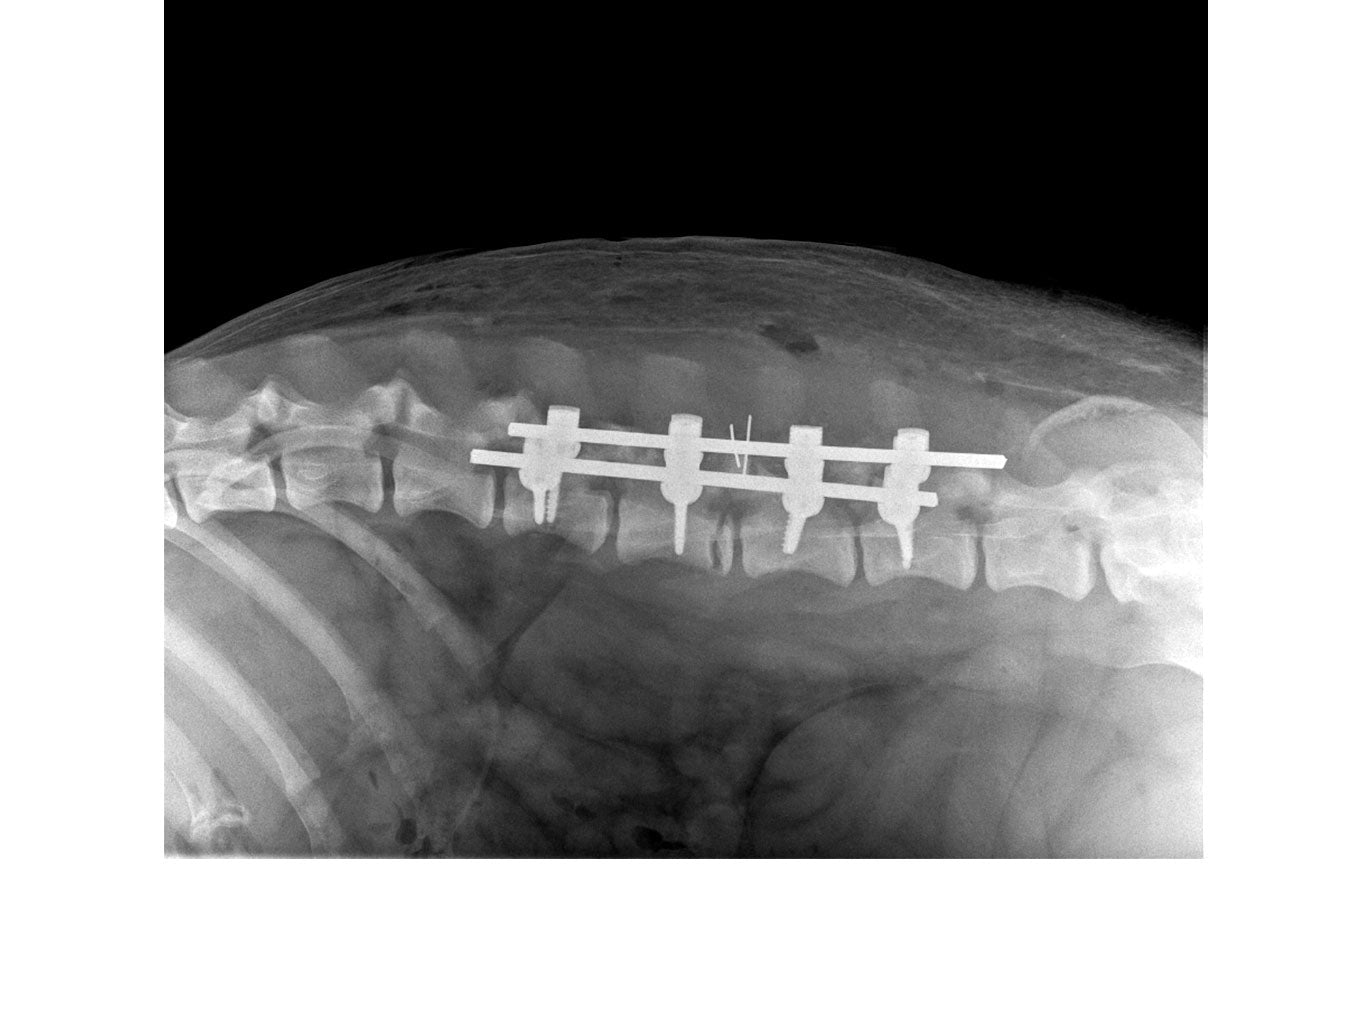

• Polyaxial screws with ball design with multiple degrees of freedom to increase screw placement options and allows placement in many different fashions

• System consists of screws, caps and rods

• Bars can be contoured if needed

// User Cases

Highlighting the cases of these products in real-life situations is vital to demonstrating their success. Below are cases studies of long-term follow up surgeries.